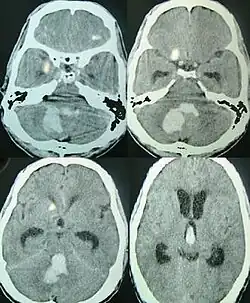

Tomografia axial mostrando hemorragia na fossa posterior[6]

Sangramentos intracerebrais são a segunda causa mais comum de AVC, representando 10% das internações hospitalares pela doença.[7] A pressão arterial elevada aumenta os riscos de hemorragia intracerebral espontânea de duas a seis vezes.[6] Mais comum em adultos do que em crianças, sangramentos intraparenquimatosos geralmente são devidos a traumatismo craniano penetrante, mas também podem ser decorrentes de fraturas de crânio deprimido. O trauma de aceleração-desaceleração,[8][9][10] ruptura de um aneurisma ou malformação arteriovenosa (MAV) e sangramento dentro de um tumor são causas adicionais. A angiopatia amiloide é uma causa não comum de hemorragia intracerebral em pacientes com idade superior a 55 anos. Uma proporção muito pequena é devida a trombose do seio venoso cerebral.